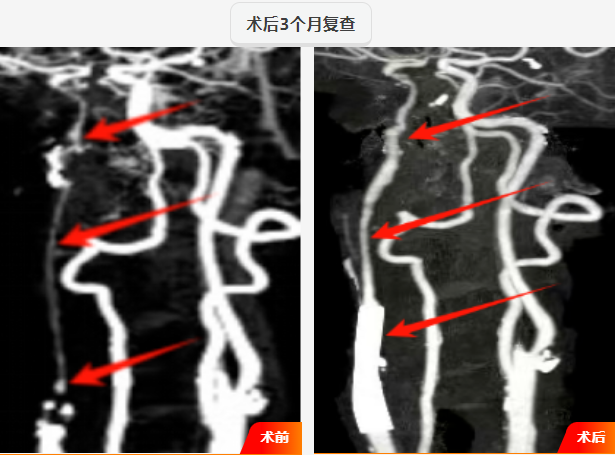

1、精准造影,锁定“元凶”:首先进行全脑血管造影(DSA),清晰显示右侧颈内动脉起始部至颅内段慢闭、重度狭窄,远端血流微弱,精准定位闭塞的部位,根据影像精准的测量出狭窄部位远端及近端血管的直径,并选择合适的支架。

2、小球囊开道:在微导丝的精确引导下,小心翼翼地穿越颈内动脉起始部至颅内段;随后,用小球囊由远及近逐步扩张,随着球囊充盈,造影显示,血流瞬间通过狭窄段,管腔恢复通畅。

3、支架精释,畅通无阻:一枚大小、长度经过精密计算的自膨式支架,在精确的影像引导下,支架被完美释放在预定位置,撑开满意;血流通畅。

4、血流奔腾,宣告胜利:最终造影结果令人振奋!颈内动脉血流完全恢复畅通,支架形态完美,位置满意,颅内远端血管显影清晰、充盈良好。